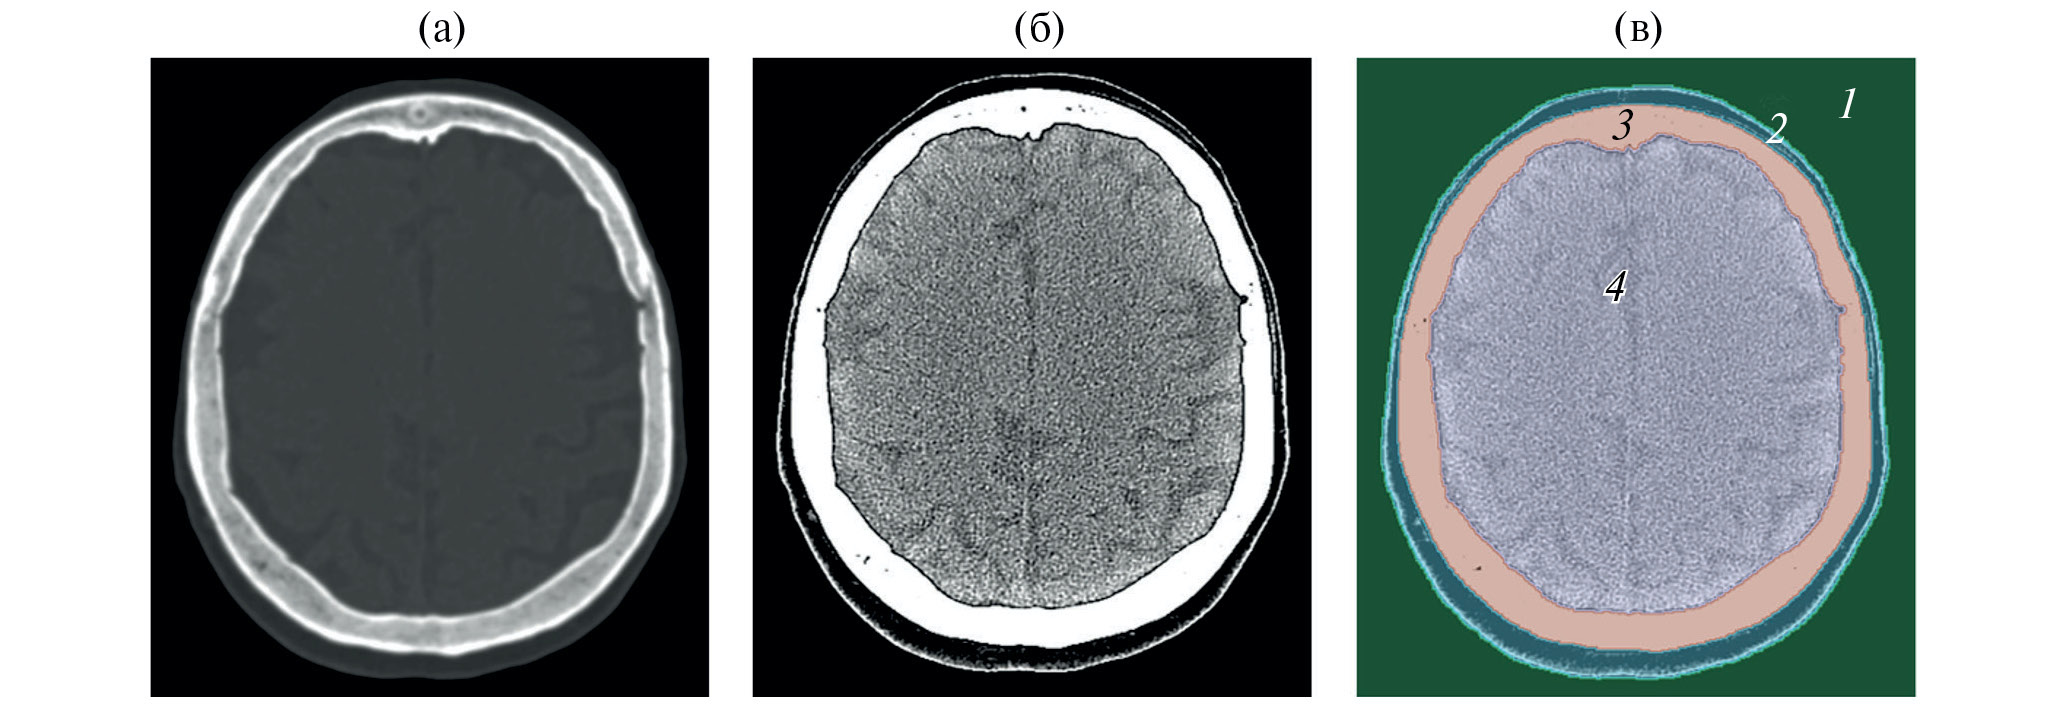

Чтобы задать коэффициент поглощения, необходимо сегментировать КТ-изображения и выделить основные сегменты – кожу, череп и мозг, коэффициент поглощения для которых известен из справочной литературы [19]. Сегментация КТ-изображений в данной работе была проведена с помощью открытого программного обеспечения Slicer (slicer.org) [20]. Благодаря сильно различающимся значениям пикселей по шкале Хаунсфилда в кости и мягких тканях, к КТ-изображению возможно было применить метод пороговой сегментации. С помощью этого метода и дополнительных функций программы Slicer (flood filling, islands, logic operations) в отдельные сегменты были выделены мозг, череп, кожа и согласующая среда (вода) (рис. 1).

Рис. 1. Аксиальный срез компьютерной томографии головы человека (а) – до проведения сегментации, (б) – до проведения сегментации с другим контрастом, (в) – после сегментации в программе Slicer. Сегменты отмечены цифрами: 1 – внешняя среда (вода), 2 – кожа, 3 – череп, 4 – мозг.